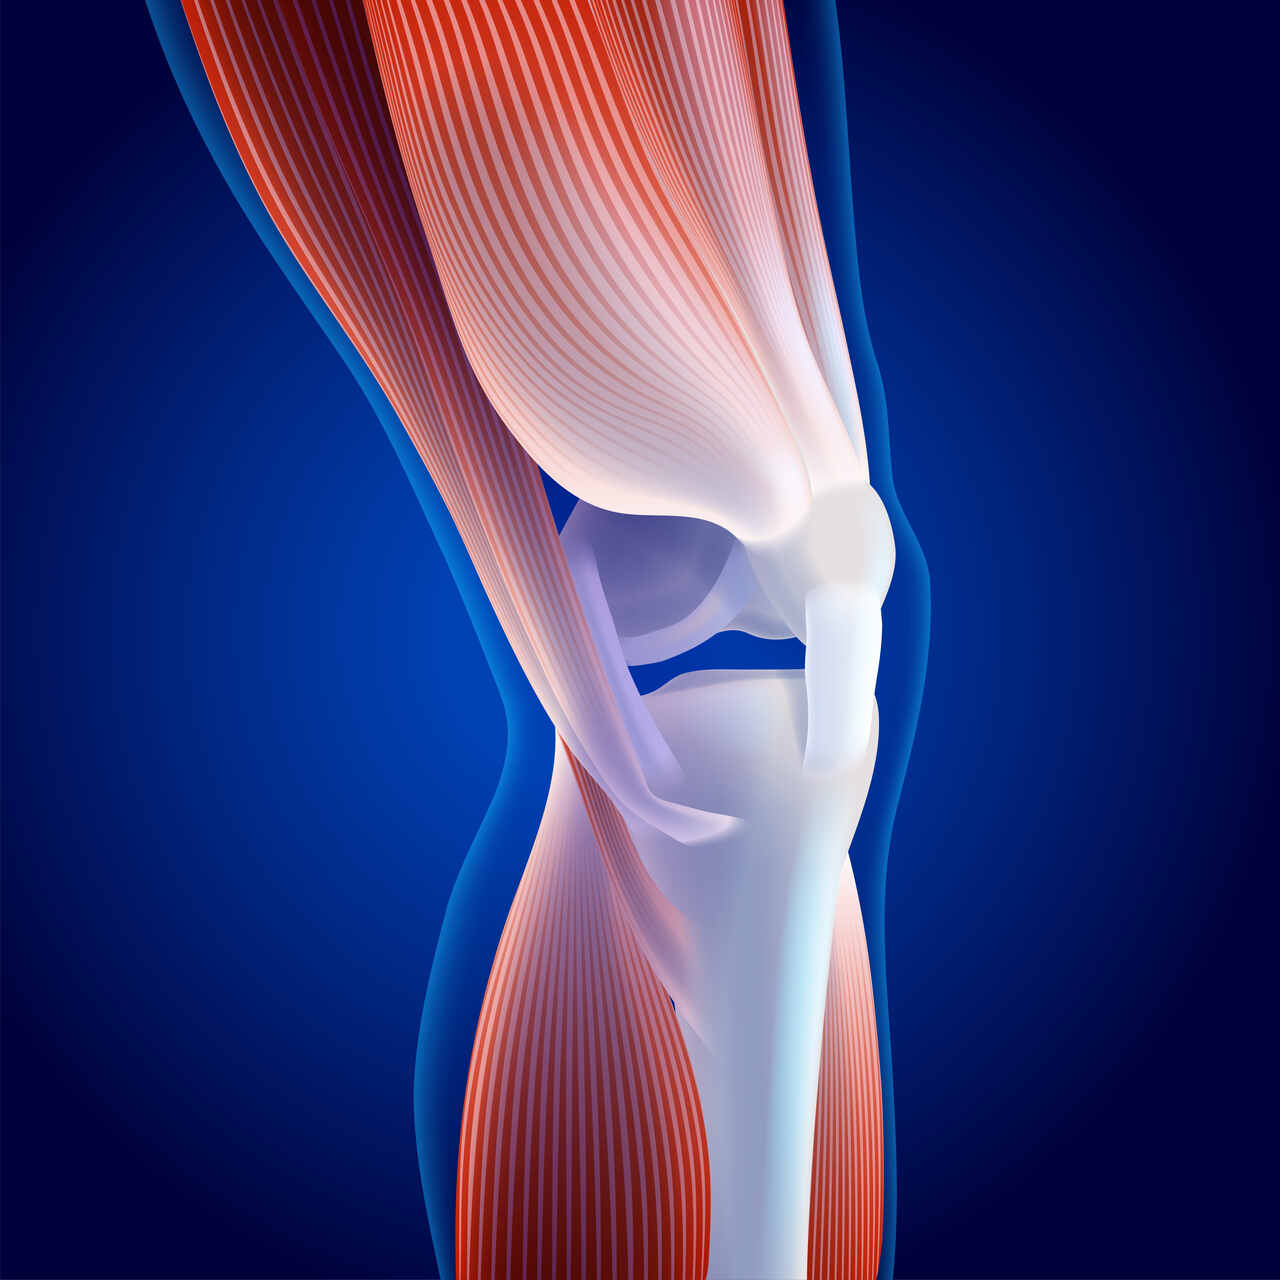

A tendinite patelar é uma das lesões mais comuns em atletas, principalmente os praticantes de esportes de impacto e que exigem frenagem constante. Ela ocorre quando o tendão que liga a patela ao osso da perna inflama devido ao uso excessivo ou movimentos repetitivos.

A tendinite patelar tem como sintomas mais comuns: dor na frente do joelho, dor que piora com movimentos de correr ou saltar, edema no joelho, dificuldade de movimentar o joelho e sensação de joelho duro ao acordar.